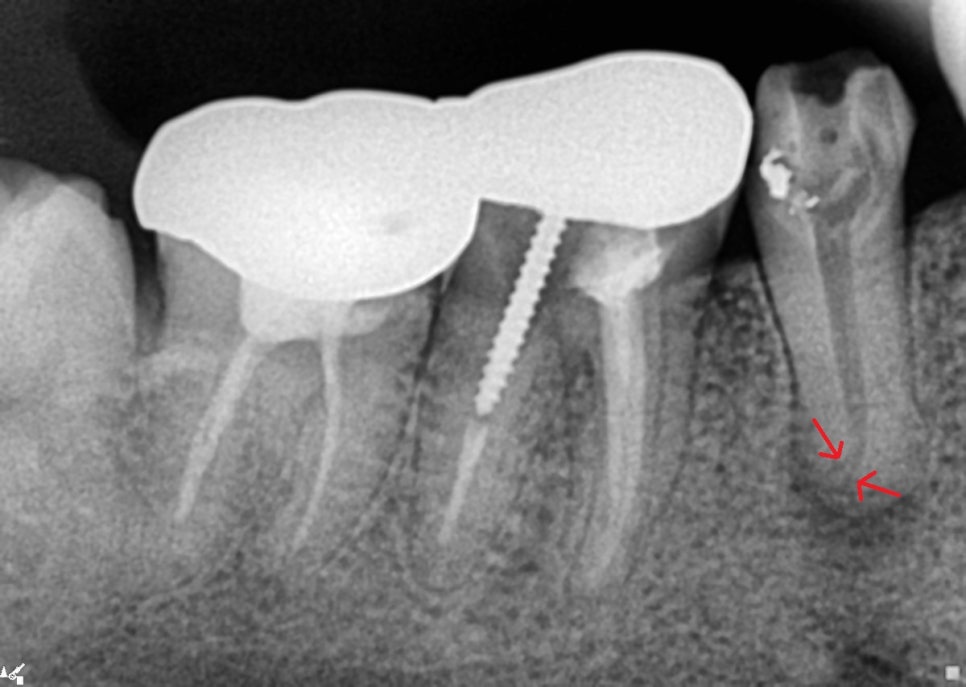

신경관 안에 있던 충전물들을 깨끗하게 제거하고 보았더니 신경관이 끝에서 두 갈래로 갈라져 있는 것이 보입니다.

이런 케이스에서는 뿌리끝을 확실히 소독하기 위해 화학적 소독을 더 많이 시행합니다.

이 환자분께서는 신경치료 내원만 6회를 오셨지만 잘 협조를 해주셔서 충분한 소독시간을 가질 수 있었습니다.